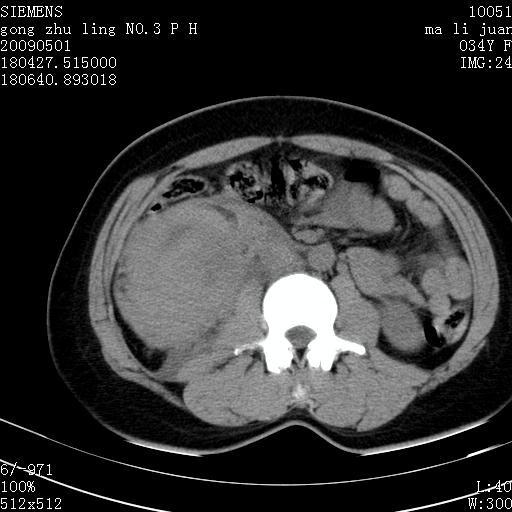

标题: CT19733:右肾碎裂 [打印本页]

标题: CT19733:右肾碎裂

青年女性,骑摩托车摔伤。

右肾碎裂伤,包膜下血肿。

术中仅见右肾碎裂,肾蒂血管未见断裂。